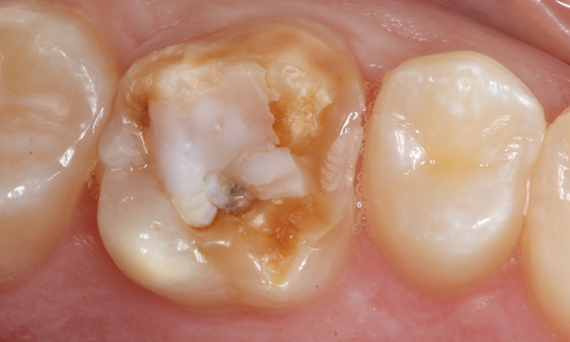

Primer molar superior en 60 minutos

Corona individual IPS.emax CAD

El caso clínico demuestra la rapidez y eficiencia con la que CEREC Primemill permite fabricar una corona de vitrocerámica de superficie completa chairside en una sola sesión, al mismo tiempo que cumple con las demandas estéticas más altas.

Antes: Insuficiencia grande del relleno de composite en el diente 16 con grietas marginales distales en la cresta, una grieta en la pared lingual y caries recurrente distal.

Después: Corona de vitrocerámica de superficie completa altamente estética.

Dra. Karyn M. Halpern DMD, MS

Nueva York, EE. UU.